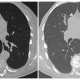

(A) Maximum Intensity Projection görüntülerde nodüllerin daha göze çarptığı ve nodül saptanmasını kolaylaştırdığını görmekteyiz. (B) Minimum Intensity Projection görüntülerde ise hava hapsi alanları daha belirgin olarak izlenmektedir.